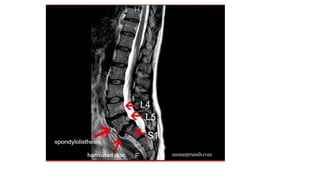

Investigation: